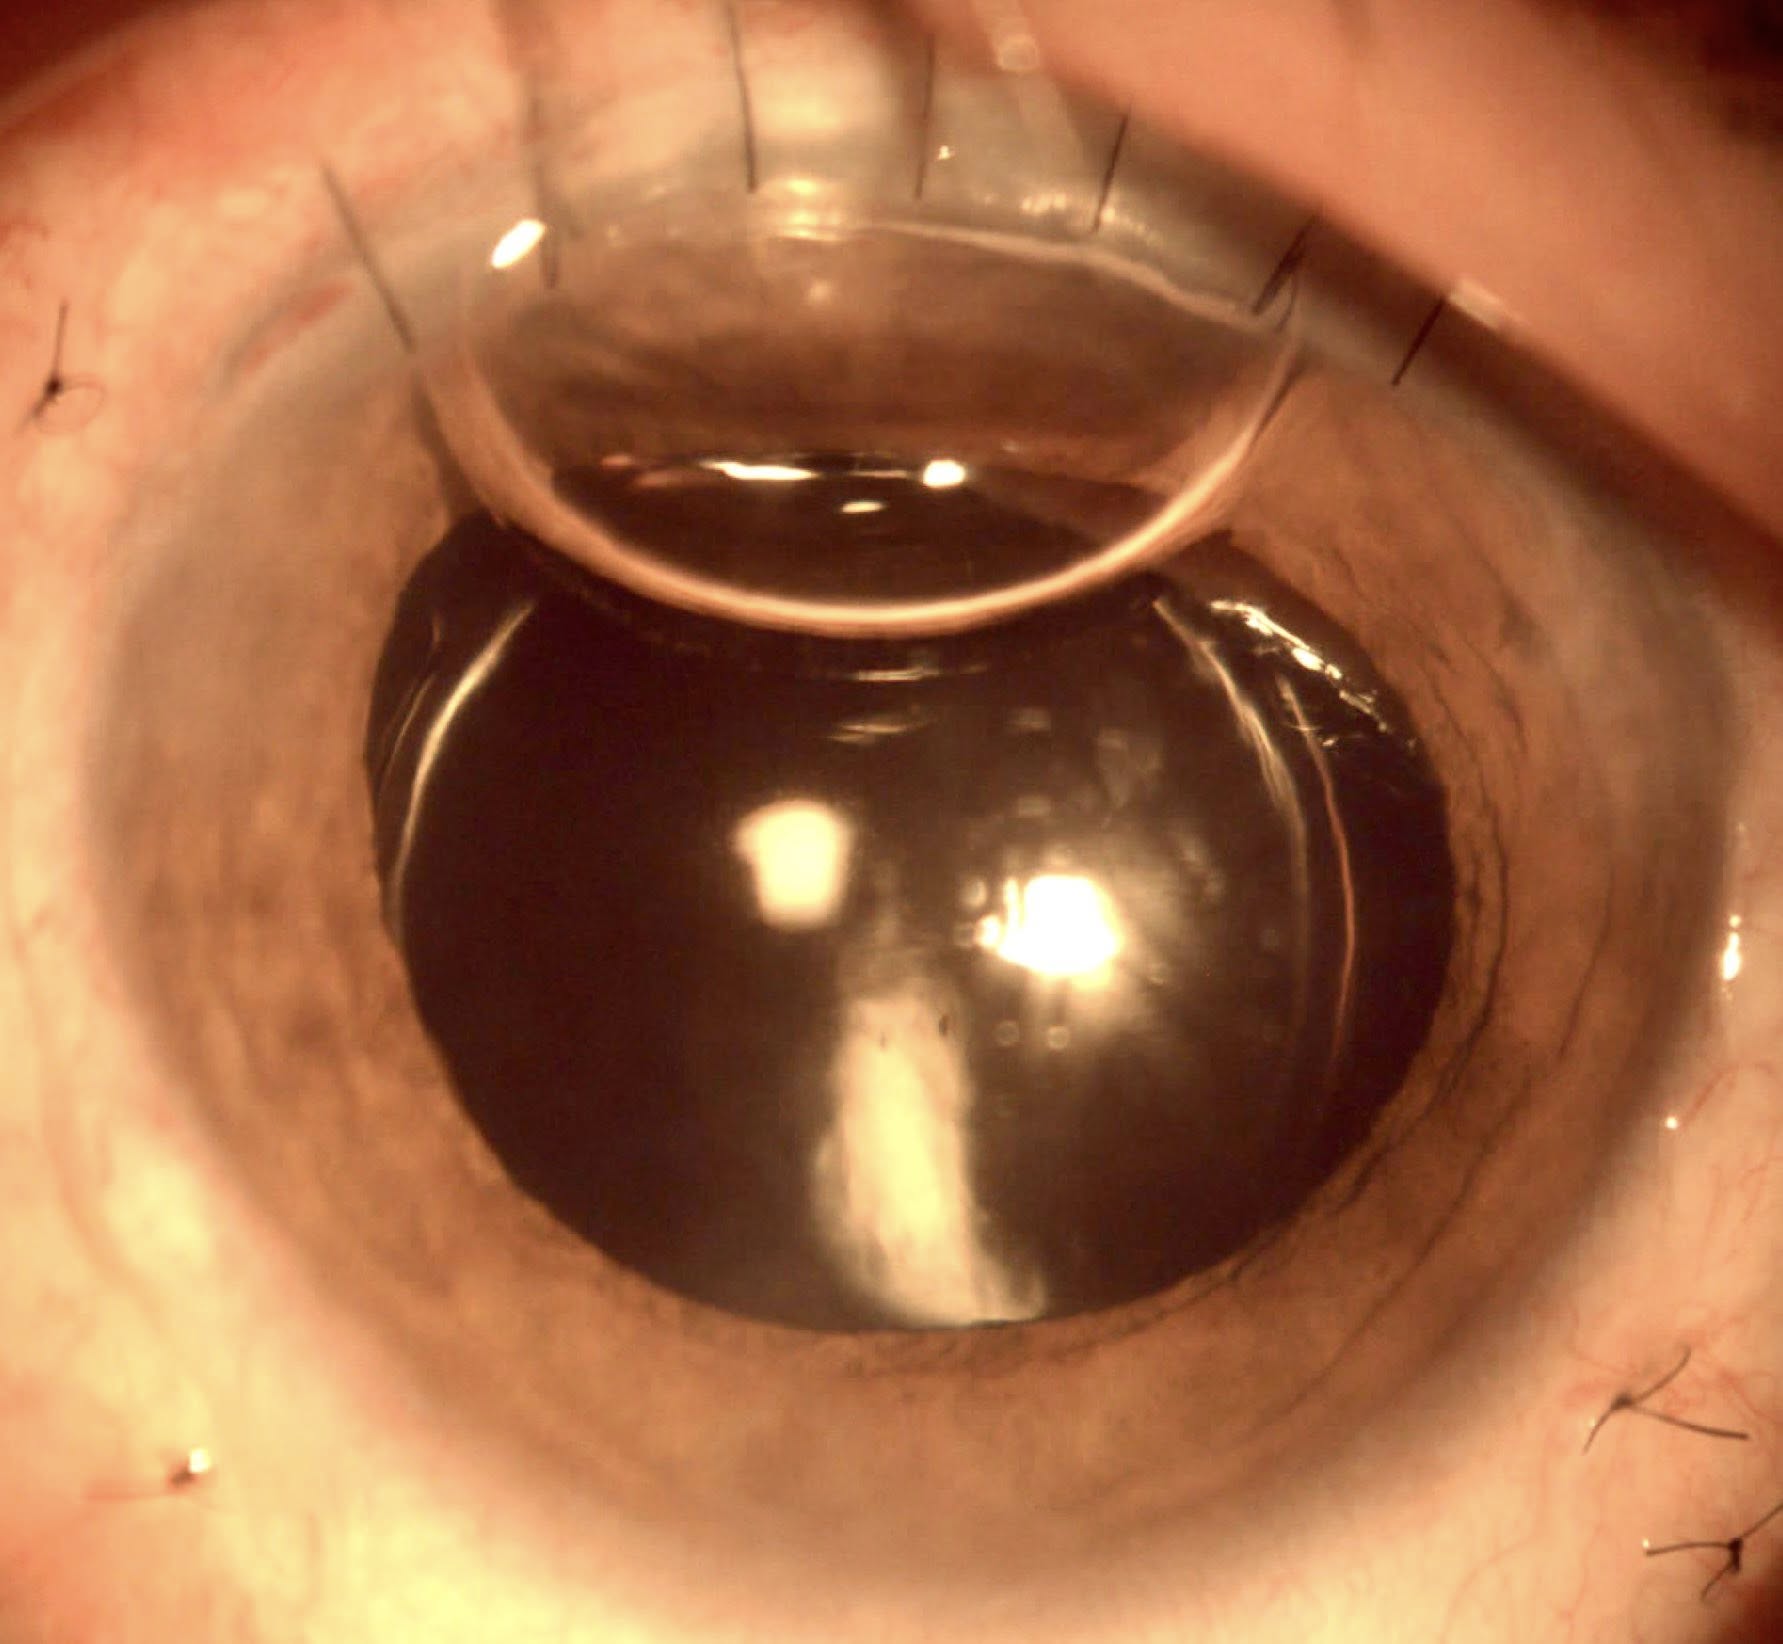

Cazul prezentat aici, deși pentru dr. Ozana Moraru nu a fost unul foarte deosebit, a fost, în schimb, pentru tinerii colegi, specialiști sau rezidenți, care au asistat la operație și, cu siguranță, a fost și pentru pacientă, victimă a violenței domestice, complet nevăzătoare din cauza traumatismelor repetate în zona feței și a ochilor, care au dus la cataractă hipermatură cu subluxație dein cristal la ambii ochi, unul fiind definitiv pierdut, prin glaucom secundar absolut. Legat de tinerii medici observatori, au avut ocazia să vadă o tehnică chirurgicală mai rar efectuată în zilele noastre, fiind mai veche, dar mereu actuală în aceste situații: tehnica intra-capsulară, prin care cristalinul opac și deplasat este extras “în bloc”, pe o incizie de 7-8 mm, care necesită a fi “cusută”, iar cristalinul artificial este unul special, adaptat lipsei de suport, trebuind prins prin diverse tehnici, fie la peretele ocular, fie la iris.

Fotografiile ochiului de azi, din prima zi postoperator (ultimele patru foto), arătau excelent, cu corneea fără pic de edem și cristalinul artificial perfect centrat și, mai mult decît atât, după consultație, stând în sala de așteptare fără pansament, pacienta se uita la televizorul din sală și comenta cu fiica ei ceea ce vedea acolo!